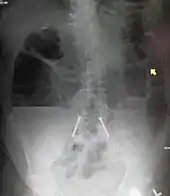

Radiological signs of bowel obstruction include bowel distension and the presence of multiple (more than six) gas-fluid levels on supine and erect abdominal radiographs. Ultrasounds may be as useful as CT scanning to make the diagnosis.[17]

Contrast enema or small bowel series or CT scan can be used to define the level of obstruction, whether the obstruction is partial or complete, and to help define the cause of the obstruction. The appearance of water-soluble contrast in the cecum on an abdominal radiograph within 24 hours of it being given by mouth predicts resolution of an adhesive small bowel obstruction with sensitivity of 97% and specificity of 96%.[18]